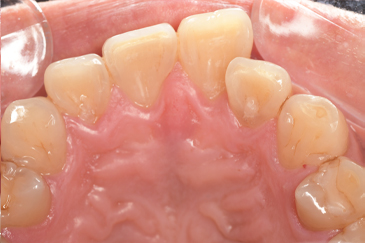

クリーニングの症例

現在の治療費と異なる場合がございます。最新の治療費は料金表をご確認ください。CASE 1

Before

After

基本情報

| 主訴 | 見た目をきれいにしたい |

| 治療期間 | 6ヶ月 |

| 治療費 | ジルコニアボンド(セラミックの被せもの)¥165,000×7(税込み) オフィスホワイトニング4回 ¥4,400×4(税込み) ホームホワイトニング¥11,000 |

| リスク・副作用 | かみ合わせがとても強い方の場合、稀に割れてしまうことがあります。 |

| 先生からの提案 | 上の前歯6本と右下の2番目の歯はセラミックの被せもので治療。 残りの下の前歯5本はプラスチックの材料で虫歯を治療し、 ホワイトニングをおこないました。白くなったご自身の歯の色に合わせてセラミックの 被せものを作成しています。 模型上で完成後をシュミレーションし、上の歯茎の位置をきれいに見えるように 揃えています。(外科処置はしていません) |